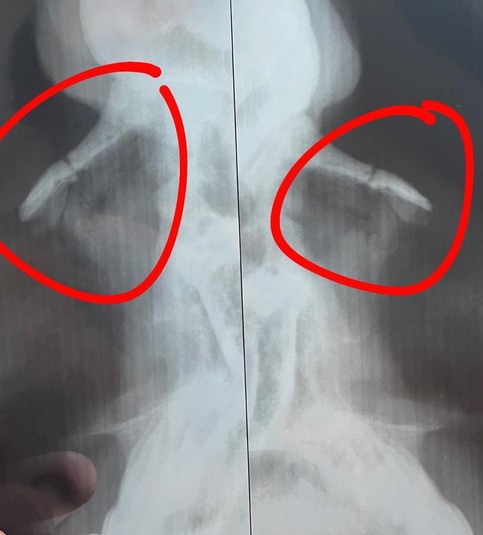

Звезда «Черного ворона», который недавно отпраздновал 31-летие, в своем Instagram сообщил, что во время съемок нового фильма ему случайно сломали нос в двух местах и наложили швы.

Также артист добавил к своему посту рентгеновский снимок, на котором видно его травму, из-за которой вынужден находиться на больничном.

«Теперь меня ждет минимум неделю больничного режима. Поскольку нет смещение кости, нужно тщательно следить за носом, чтобы оно так и срослось. Прописали пять препаратов: мажу, пшикайте. Продюсерам проектов, в которых я задействован, конечно, не очень приятно, потому что пару недель были расписаны без выходных, но жизнь внесла свои коррективы. Более того, от таких ситуаций ни один актер не застрахован. Но, конечно, этот опыт следует принять во копилки и сделать правильные выводы. Поэтому, друзья, берегите себя и своих коллег. Будьте здоровы!», - добавил Цимбалюк.